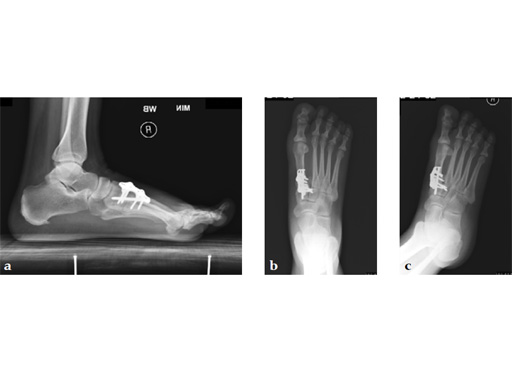

A 48-year-old woman, with hallus valgus and hypermobile medial column, also resulting in pes plano abductovalgus (flatfoot).

Case provided by Andrew Sands, New York, New York, USA

Surgery consisted of first TMT and intertarsal corrective osteotomy plus fusion with movement of the first MT lateral and plantar. This corrects the hallus valgus as well as the PPAV (and stabilizes the medial column).